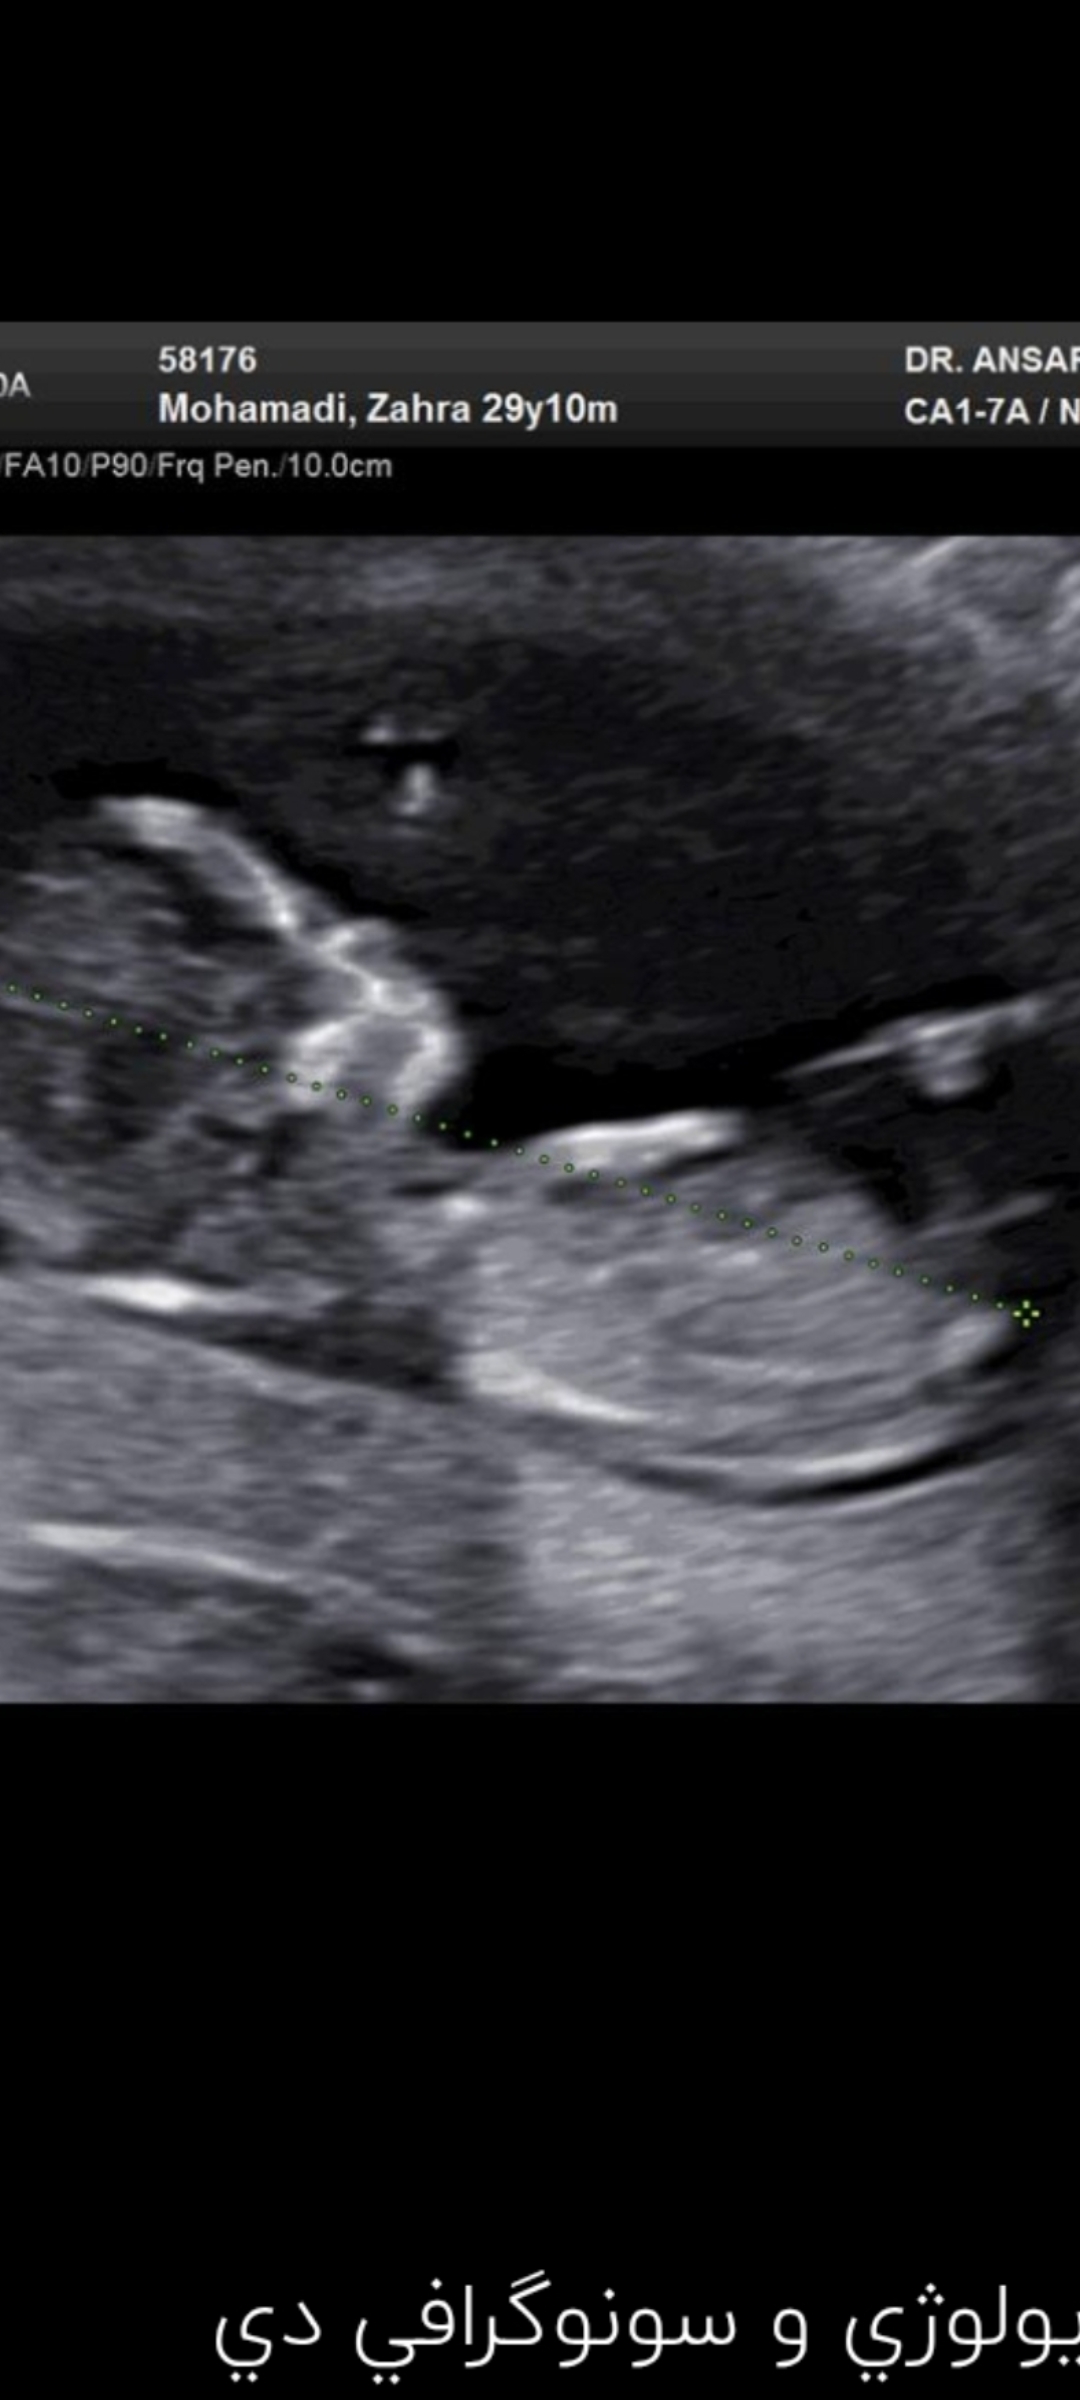

آنیییییییی مدیر استارتر عضویت: 1404/04/12 تعداد پست: 46 عنوان بارداری 34 بازدید | 2 پست مامان های عزیز جنسیت بچه توی ۱۵هفته دقیق معلومه؟به من تو انتی احتمال داد جنسیت رو شما از عکس چجوری حدس میزنید؟ 1404/04/15 | 12:13 0 نفر لایک کرده اند ... گزارش تاپیک نامناسب